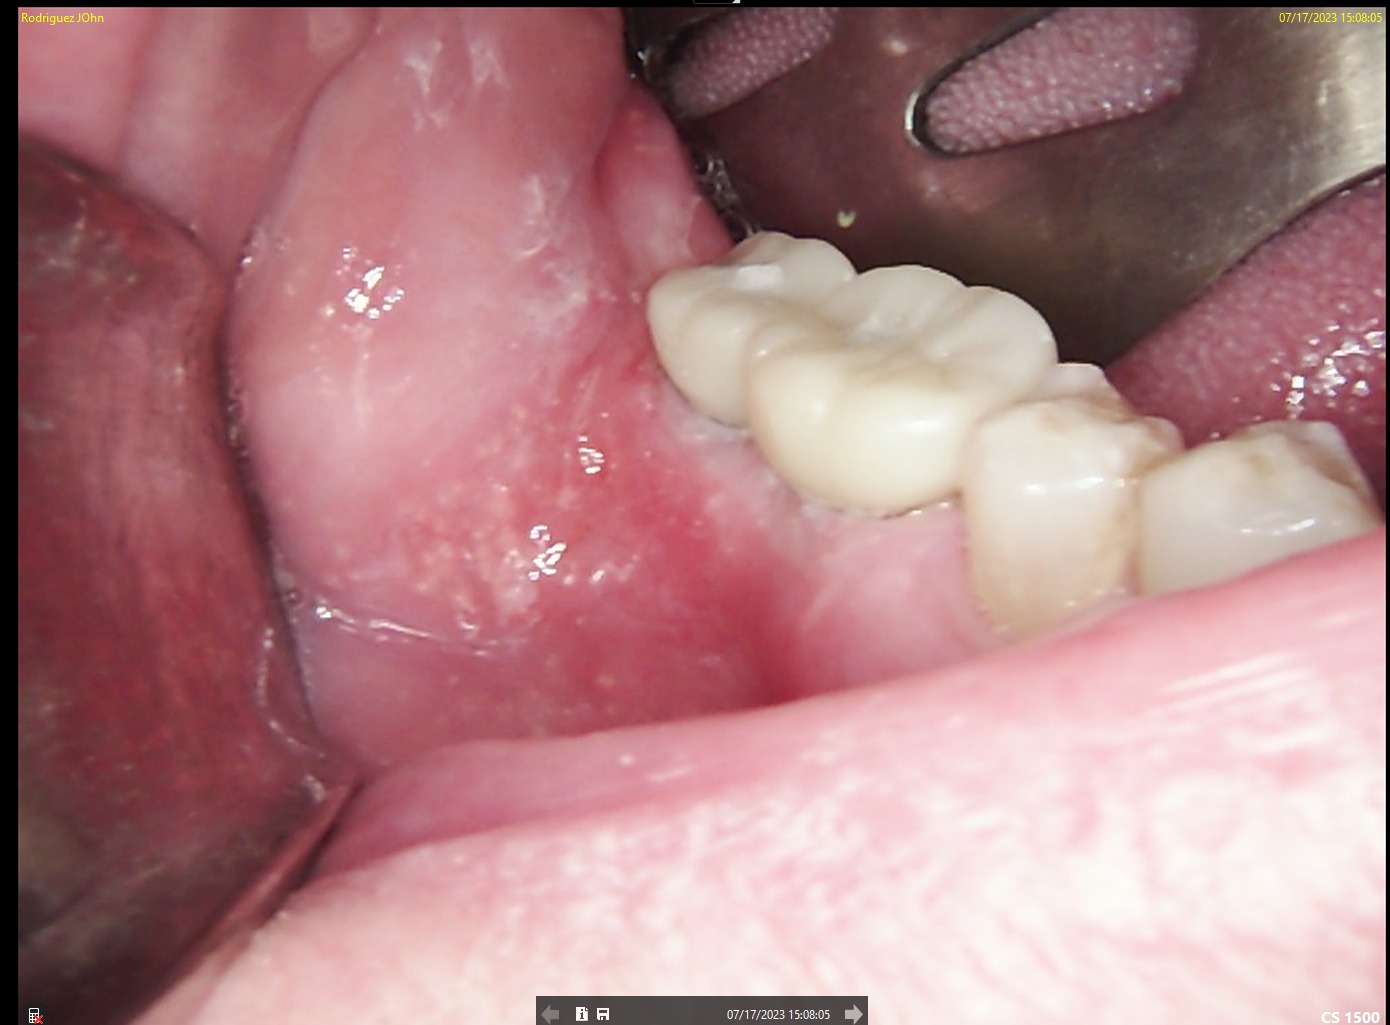

INITIAL STATE

CBCT imaging was used for precise implant planning, including evaluation of bone volume and anatomical landmarks. Digital planning allowed optimal implant positioning to ensure long-term stability and prosthetic-driven placement. Intraoral and periapical images confirmed the clinical condition prior to surgical intervention.